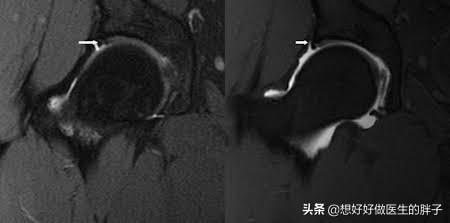

而且不代表进行了x线检查,就完全排除了患者的问题,有的时候早期的病变或者是髋关节软组织的问题,在x线上是不显影的,所以我们也建议有髋痛的患者要进行髋关节的核磁检查,如果是单侧的髋关节疼痛,甚至应该进行单侧的髋关节核磁检查。因为单髋的核磁检查可以更好的判断髋关节盂唇是否撕裂。